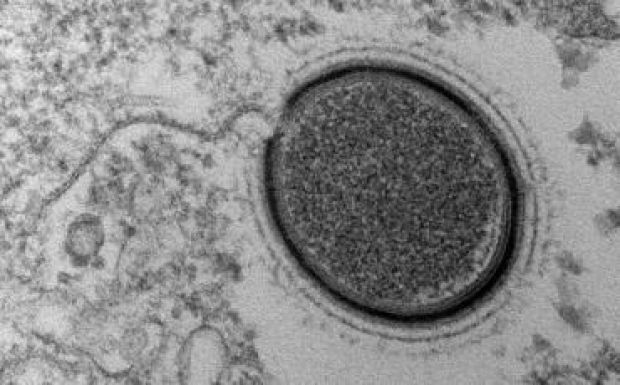

A fekete himlő vírust csak két helyen tárolják a Földön: a Vectorban és egy atlantai kutatóintézetben.